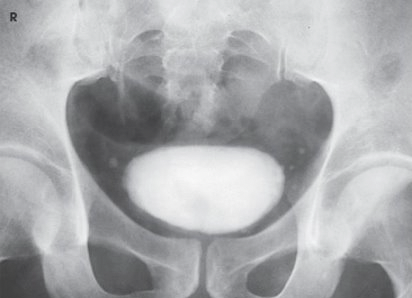

What is this projection and what is the CR angle?

AP axial with CR angled 10-15 degrees caudal